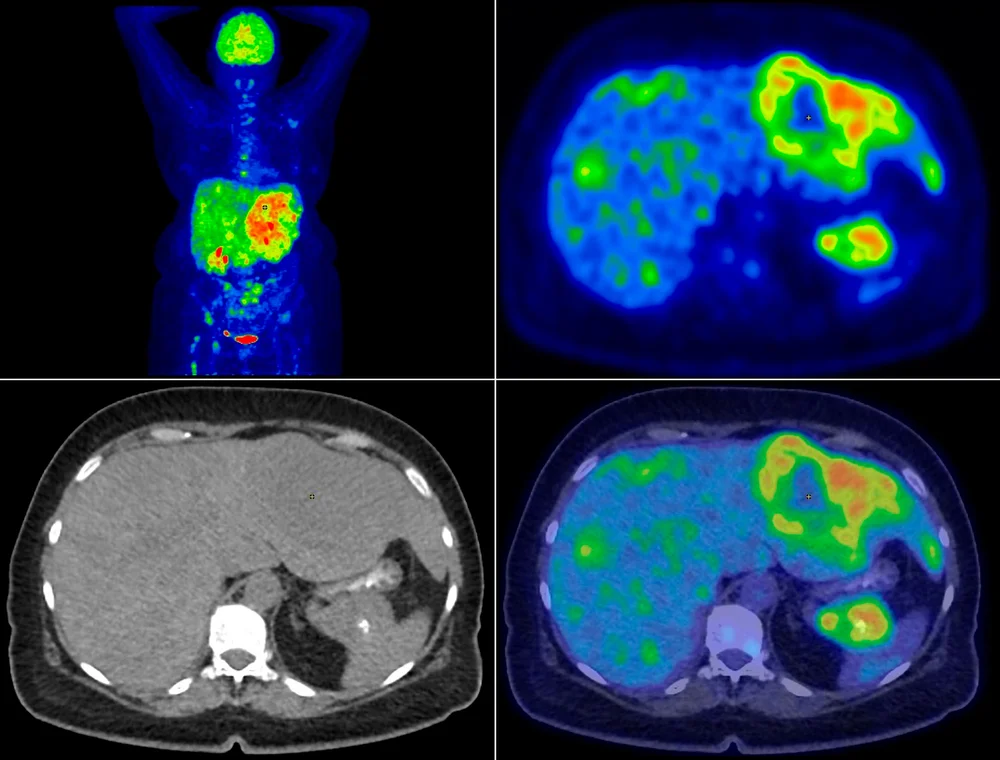

췌장암 초기증상 | 힐링오아시스